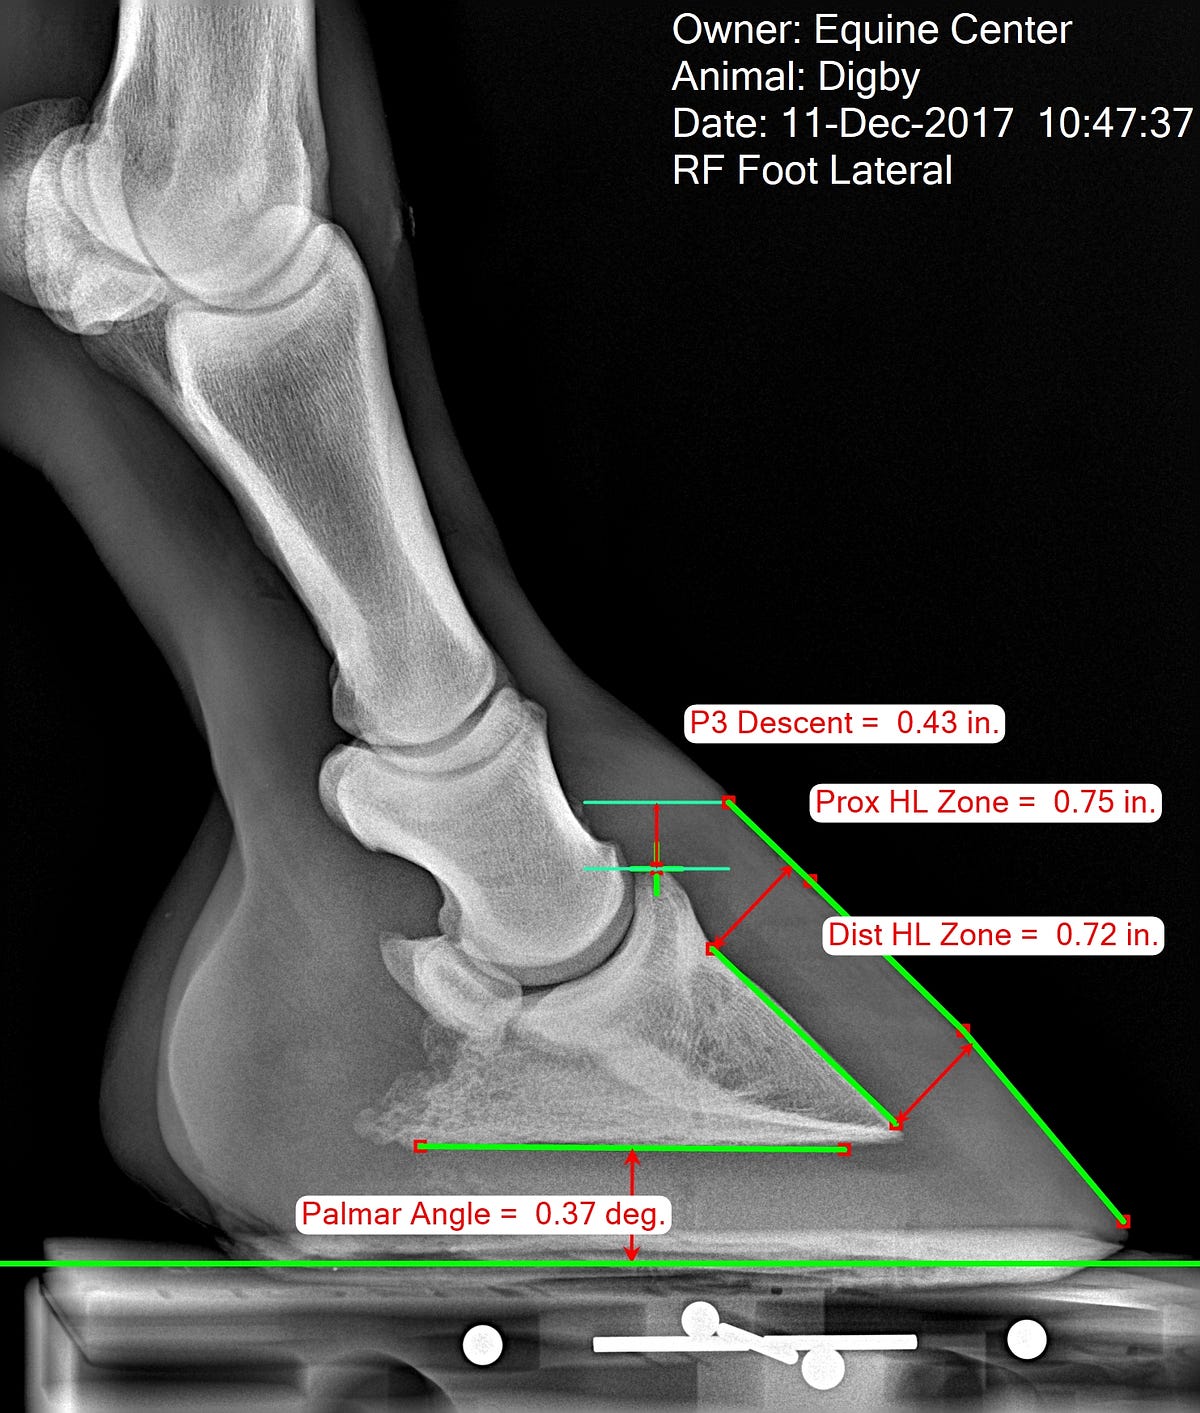

Hoof Radiographs They Give You XRay Vision Part One EasyCare Hoof

Measuring the Equine Hoof in Radiographs — a Focus on Calibration by Normal Hoof Vs Laminitis In severe cases, it can progress to founder, in which the hoof and coffin. Horses with the most severe cases of laminitis often develop poor body condition and pressure sores. The hallmark clinical sign is severe lameness with bounding digital pulses. Horses with pain equally severe in all four feet may have a normal stance. Laminitis is inflammation and damage. Normal Hoof Vs Laminitis.